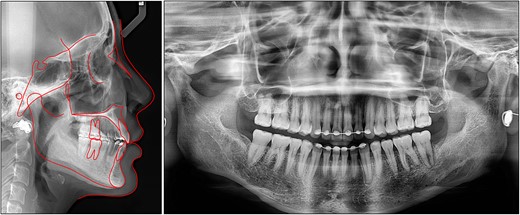

On an extraoral evaluation, the patient had a slightly increased lower anterior facial height with a right deviated mandible (Fig. 1). The lateral view showed a flat profile with a normal nasolabial angle. No sign of a temporomandibular joint disorder was detected.

On a lateral cephalometric evaluation, the patient had a skeletal class I relationship (point A-nasion-point B angle, 4.0°) with a hyperdivergent facial pattern (Frankfort mandibular angle, 32.5°) (Table 1). The panoramic radiograph showed the presence of all teeth including the third molars (Fig. 2). The patient was diagnosed with an iatrogenic open bite and class II malocclusion on a skeletal class I relationship.